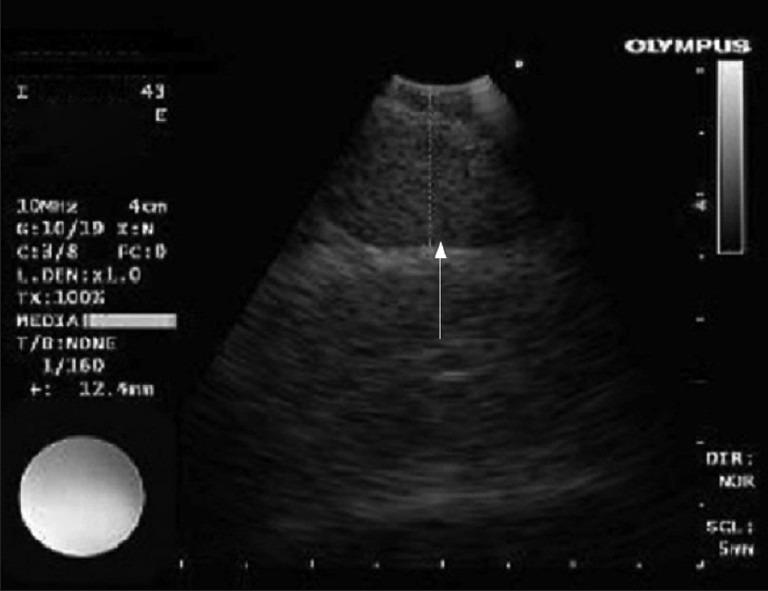

Crazy-paving sign is a pattern seen on multislice computed tomography images of the lungs. It is characterized by a reticular pattern superimposed on ground-glass opacity. It was first described in the late 1980s in patients with pulmonary alveolar proteinosis, but has now been described in some other diseases of the lung. Enlarged mediastinal lymph nodes can be seen in infectious and specific inflammatory diseases and malignancies. The present report describes a case of a 44-year-old man in whom congestive heart failure presented with a crazy-paving appearance and enlarged lymph nodes of the lungs on the chest computed tomography scan.

碎石路征是在肺部多层计算机断层扫描图像上看到的一种表现形式。其特征是网状影叠加在磨玻璃样密度影上。它于20世纪80年代末首次在肺泡蛋白沉积症患者中被描述,但现在在其他一些肺部疾病中也有报道。在感染性疾病、特异性炎症性疾病和恶性肿瘤中可见纵隔淋巴结肿大。本报告描述了一名44岁男性病例,其充血性心力衰竭在胸部计算机断层扫描中表现为碎石路征及肺部淋巴结肿大。